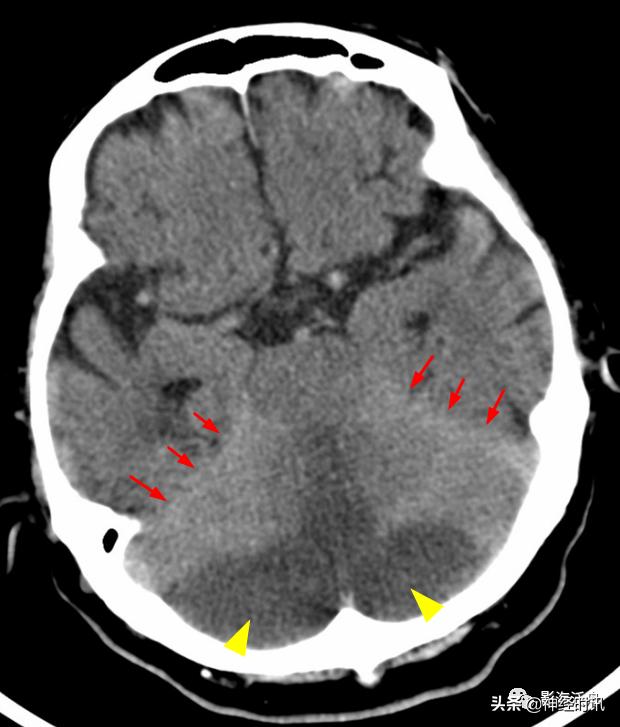

闭合性头颅外伤后,患者双侧大脑半球的多个脑回出现挫伤(红箭),损伤脑组织邻近的脑沟、脑裂少量积血,此即蛛血。由此可见蛛血的本质是脑表层(即脑灰质)挫伤后,血液沿破损的软脑膜流入到蛛网膜下腔,并在血清蛋白收缩作用下凝聚所致。也就是说,在凝血功能正常的情况下,程度较轻的外伤性蛛血引发大出血的概率极低。